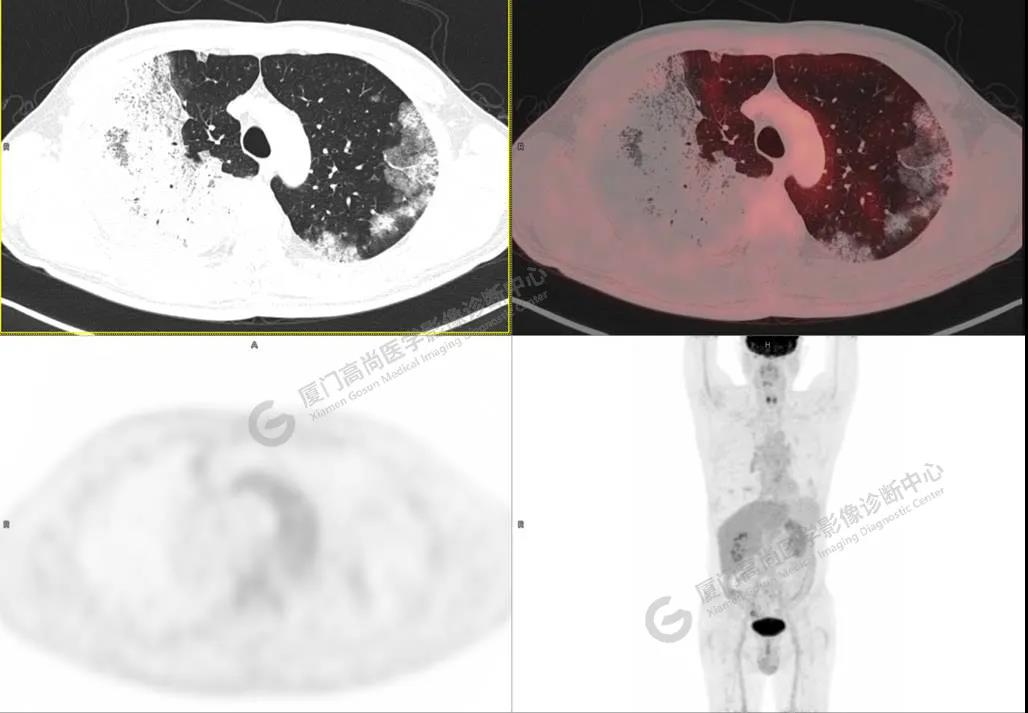

PET/CT影像圖

圖1

PET/CT所見(jiàn):雙肺大片實(shí)變影及磨玻璃影,部分呈地圖樣改變,累及右肺尖,部分放射性攝取輕微增高,SUVmax 1.77,其內(nèi)見(jiàn)多發(fā)支氣管充氣征象。

影像診斷: 雙肺大片實(shí)變影及磨玻璃影,大部分代謝不高,局部代謝輕微增高,考慮肺泡蛋白沉積癥,建議病理學(xué)檢查或肺泡灌洗物檢查。